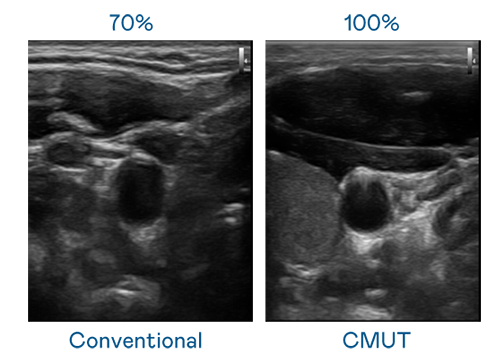

CMUT 技术是一种用电容式微机电元件来产生超音波讯号的技术。与传统 PZT 压电式技术相比,CMUT 频宽增加 30%,更宽频的超音波讯号让影像解析度大幅提升,是实现高影像品质医疗超音波扫描、促进精准医疗发展的关键技术。

超音波影像的解析度高低,首先取决于探头能发出的讯号频宽。非凡娱乐 CMUT 可提供高清晰的超音波讯号,提供高频宽、高灵敏度、影像纹理细节更高的超音波影像,协助医护人员缩短影像判读时间及利用精准的医疗影像进行诊断。